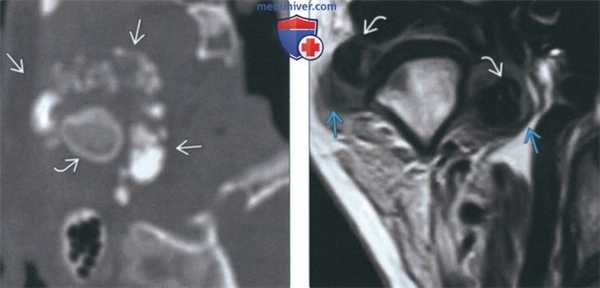

(Слева) На аксиальной КТ у этого же пациента вдоль внутреннего, наружного, переднего края мыщелка визуализируются множественные обызвествленные/оссифицированные свободные тела различного размера. Су аавная капсула в значительной степени растянута.

(Справа) На косом корональном срезе (Т1) у этого же пациента в пределах растянутой капсулы визуализируются обызвествленные/оссифицированные свободные тела.

4. МРТ при первичном синовиальном хондроматозе ВНЧС:

• Т1 ВИ:

о МРТ позволяет дифференцировать тканевые пластинки между объемным образованием и окружающими мягкими тканями:

- Дает возможность отличить хондроматоз ВНЧС от опухоли околоушной железы

- В случаях интракраниального распространения позволяет исключить поражение височной доли

о Множественные гипоинтенсивные узлы в верхнем суставном пространстве

о Утолщение синовиальной оболочки

о Сепарация от суставного диска

• Т2 ВИ:

о Выпоте верхнем суставном пространстве ± вздутие:

- Слегка неоднородный гиперинтенсивный сигнал в неоссиицированных/необызвествленных хрящевых узлах

о В редких случаях выпот не обнаруживается, может наблюдаться сигнал неоднородной интенсивности, свидетельствующий о мягкотканном образовании или хрящевых узлах о Кольцевидный сигнал: гиперинтенсивная жидкость вокруг скоплений гипоинтенсивных узлов

• Т1 ВИ С+:

о Контрастное усиление синовиальной оболочки